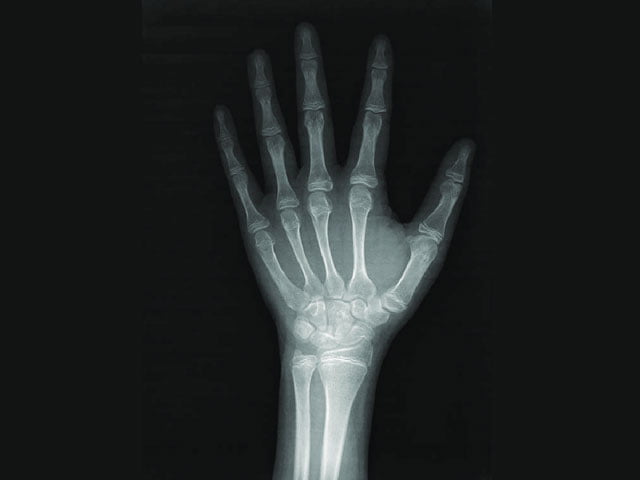

Kemik yaşı araştırması, doktorların bir çocuğun iskelet sisteminin olgunluğunu tahmin etmesine yardımcı olur. Genellikle sol bileğin, elin ve parmakların tek bir röntgeni çekilerek yapılır. Az miktarda radyasyon kullanan güvenli ve ağrısız bir işlemdir. Röntgen görüntüsündeki kemikler, aynı cinsiyet ve yaştaki çok sayıda diğer çocuktan alınan verilere dayanan standart bir kemik gelişimi atlasında X ışını görüntüleriyle karşılaştırılır.

Kemik yaşı yıl olarak ölçülür. Bir çocuğun parmakları ve el bileğindekiler gibi kemiklerinin her iki ucunda büyüme plakaları adı verilen “büyüme bölgeleri” bulunur. Bu plakalar, kemiklerin uzunlamasına büyümesinden sorumlu özel hücrelerden oluşur. Büyüme plakalarının bir röntgende fark edilmesi kolaydır, çünkü daha yumuşaktırlar ve daha az mineral içerirler, bu da onları bir röntgen görüntüsünde kemiğin geri kalanından daha koyu gösterir.

Çocuklar büyüdükçe, büyüme plakalarının X-ışını görüntülerinde görünümü değişir ve incelir, sonunda kaybolur (buna “kapalı büyüme plakaları” denir). Her yaşta farklı göründükleri için, doktor kemiklerin ve büyüme plakalarının görünümüne göre bir kemik yaşı belirleyebilir.

Bir çocuğun kemik yaşı (iskelet yaşı olarak da adlandırılır), atlastaki standart X-ışını görüntülerinden hangisinin çocuğun kemiklerinin röntgen üzerindeki görünümüne en yakın eşleştiğini belirleyerek belirlenir. Bir çocuğun kemik yaşı ile kronolojik yaşı arasındaki fark, bir büyüme sorununa işaret edebilir. Ancak bu tür farklılıklar her zaman bir sorun olduğu anlamına gelmez, çünkü mükemmel sağlıklı çocuklar kronolojik yaşlarından farklı kemik yaşlarına sahip olabilirler.